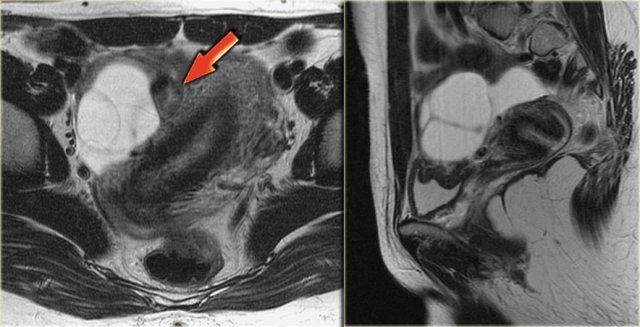

Axial and sagittal T2W images from the same patient.

The right ovary contains multiple simple T2 bright cysts with thin borders and no solid components.

On the axial image there is one lesion, that is dark on T2, i.e. a complex cyst (arrow).

There is a small amount of ascites around the right ovary, but not enough to raise concern of a possible neoplasm.

On the T1-weighted image without fatsat the complex cyst is bright, indicating either fat or blood content.

On the T1-weighted image with fatsat the lesion remains bright, ruling out a fatty lesion.

After the administration of Gd there is no enhancement, confirming that this is a hemorrhagic ovarian cyst.

An endometrioma would be in your differential.

Note that subtraction images are best to demonstrate the lack of enhancement in a lesion, that is bright on the pre-contrast T1-weighted image.